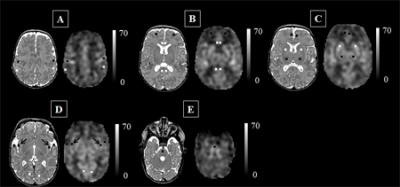

The researchers used arterial spin labeling (ASL) MRI to label water and map how blood flows through infants' brains to detect which regions do or do not receive adequate blood supply. With ASL-MRI, scans can be performed without a contrast agent because water from arterial blood illuminates the path traveled by cerebral blood. The technique also appears to make an abnormality more visible than conventional imaging does.

"The ongoing maturation of the newborn's brain can be seen in the distribution pattern of cerebral blood flow, with the greatest volume of blood traveling to the brainstem and deep gray matter," said lead author Marine Bouyssi-Kobar. "Because of the sharp resolution provided by ASL-MRI, our study finds that in addition to the brainstem and deep gray matter, the insula and the areas of the brain responsible for sensory and motor functions are also among the most oxygenated regions."